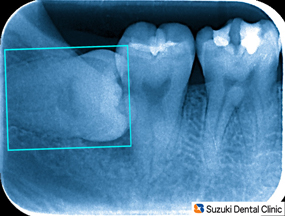

ちらっと見える親知らず 30代の男性。主訴は「親知らずの所に物がよく詰まる。抜歯して下さい」でした。

Dr;「親知らずは、横向きに生えていますが一部だけ見えています。この隙間を歯磨きでキレイに保つのは難しいです。食べ物が挟まったまま放置しておけば手前の歯まで虫歯になります。ガンバって抜歯を致しましょう!」

横向きに埋まってますので、引っ張って歯を抜くことは出来ません。難しい抜歯になりそうです。事前に抜歯方法と抜歯後に出やすい症状について説明します。